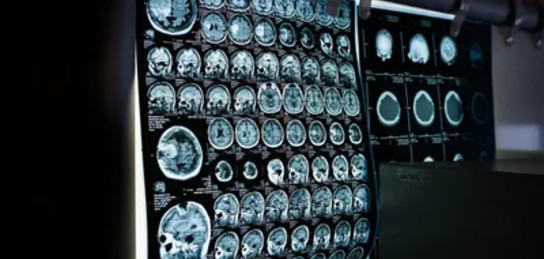

Ученые заявили, что у людей с ярко выраженными психопатическими чертами изменена структура четырех областей мозга, связанных с контролем импульсов, эмоциональной регуляцией и социальным поведением, сообщает Zakon.kz.

"Нейровизуализацию мозга провели у 39 мужчин, набравших высокие баллы по шкале психопатии PCL-R. Этот инструмент позволяет оценить два основных компонента психопатии: эмоциональную отчужденность (Фактор 1) и антисоциальное поведение (Фактор 2)", – говорится в исследовании.

После МРТ-сканирования участников, полученные данные были проанализированы с помощью Julich-Brain Atlas – цифровой карты мозга, позволяющей сопоставлять анатомические особенности с поведенческими характеристиками.

Наиболее выраженные отличия обнаружили у тех, кто набрал высокие баллы по Фактору 2. У них оказался снижен объем четырех участков мозга – базальных ганглий, таламуса островковой коры, передней поясной извилины и правой части гиппокампа. Эти области играют важную роль в регуляции эмоций, мотивации, обучении и социальном взаимодействии.

"Также в среднем общий объем мозга у людей с выраженной психопатией был на 1,45% меньше, чем в контрольной группе", – пояснили ученые.

При этом для Фактора 1 – эмоциональной отстраненности – достоверных различий в структуре мозга выявлено не было. Это, по мнению исследователей, может свидетельствовать о том, что нейробиологическая основа различных аспектов психопатии неоднородна.